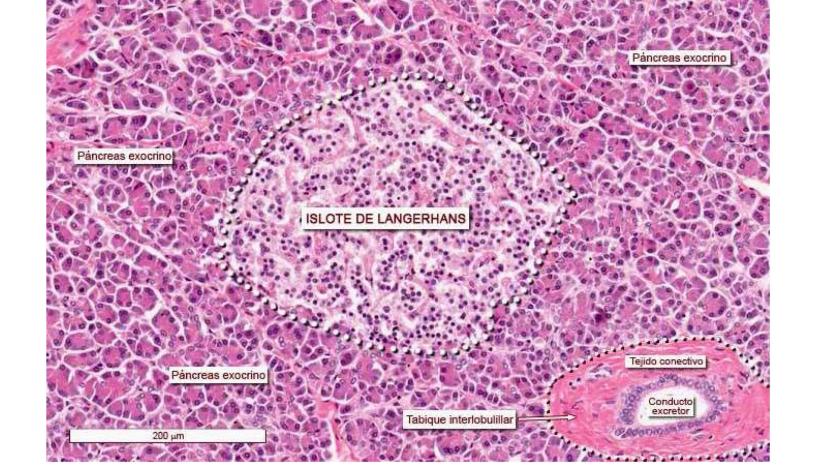

El páncreas tiene una historia de desarrollo súper interesante porque se forma de dos esbozos separados que luego se unen. Es como si fueran dos equipos trabajando por separado para crear el mismo órgano.

El esbozo pancreático dorsal surge de la parte de atrás del duodeno en la 4ta semana. El esbozo pancreático ventral aparece cerca del divertículo hepático alrededor del día 32. Estos dos "equipos" van creciendo hasta encontrarse.

Durante el desarrollo, la yema ventral se desplaza hacia la parte dorsal y se posiciona justo debajo de la yema dorsal. El proceso uncinado de la yema ventral formará la cabeza del páncreas, mientras que el resto viene de la yema dorsal.

💡 Concepto clave: Los dos conductos pancreáticos (dorsal y ventral) también se fusionan, creando el sistema de drenaje del páncreas adulto.